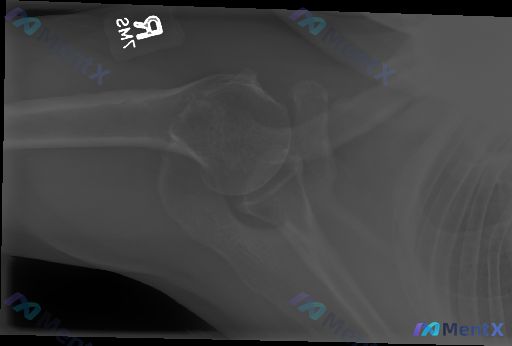

整理了一个有点意思、甚至有点“矛盾”的骨科病例,先把基础信息放出来: 基础情况:62岁女性,因持续性肩部疼痛求医。 关键矛盾点:她明确报告没有近期或过去的外伤史、感染史。 影像初步结果:右肩部X光提示—— - 肱骨近端复杂性骨折:累及解剖颈及大结节,伴有明显移位和多发骨折碎片 - 盂肱关节脱位:肱骨...